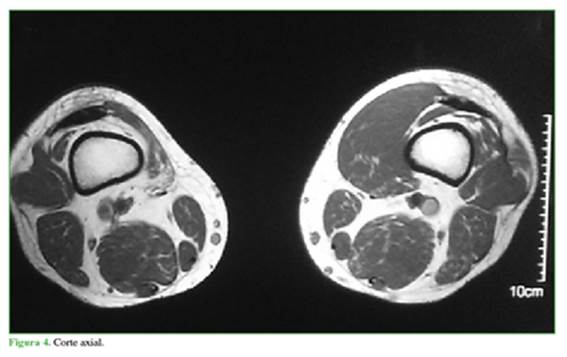

El estudio gold standard es la resonancia magnética nuclear, la que informó ausencia completa del vasto medial oblicuo (VMO) y diagnóstico presuntivo de agenesia completa de ese músculo en cortes axiales, sagitales y coronales en T1 y T2 (Figuras 4 a 8). Cortes coronales a diferentes alturas comparativas de ambos muslos en la región del tercio medio distal (Figuras 5 a 8).

Falta la representación habitual del músculo vasto medial derecho en toda su extensión, sugestivo de hipotrofia grave/agenesia muscular; vasto intermedio derecho, vasto lateral y recto anterior de grosor y señal de resonancia preservada. No se identifican alteraciones del trofismo muscular, ni señal de resolución de los músculos del grupo medial y posterior derecho, ni a nivel del muslo izquierdo. No se observan lesiones ni alteraciones del paquete vascular femoral. Llama la atención una asimetría en la masa muscular de la cara interna del muslo; no se identifica el músculo vasto medial y no hay signos de edema, colecciones, ni alteraciones de planos grasos.